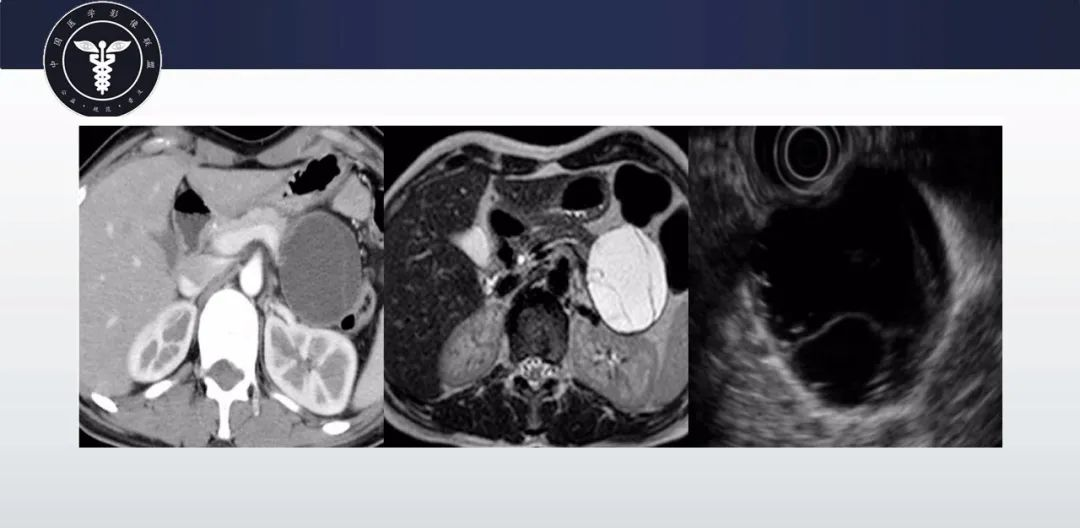

【病例】胰腺血管瘤1例CT及MR影像-9

【病例】胰腺血管瘤1例CT及MR影像-10

【病例】胰腺血管瘤1例CT及MR影像-11